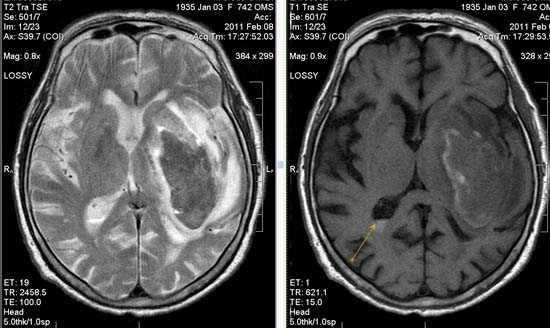

Церебральная гемиатрофия (Dyke-Davidoff-Masson syndrome)

Анамнез: Юноша, 18 лет. Когнитивные нарушения, левосторонний гемипарез с раннего детства. Два эпизода судорог за последние две недели.

Описание исследования Атрофия правого полушария головного мозга с энцефаломаляцией и глиозом в смежных отделах лобной, теменной и височной долей (бассейн правой СМА), exvacuo-дилатация правого бокового желудочка, атрофия ипсилатеральной ножки мозга, базальных ганглиев и таламуса, легкая перекрестная атрофия мозжечка (левая гемисфера), ипсилатеральное смещение срединных структур и некоторое утолщение костей свода черепа.